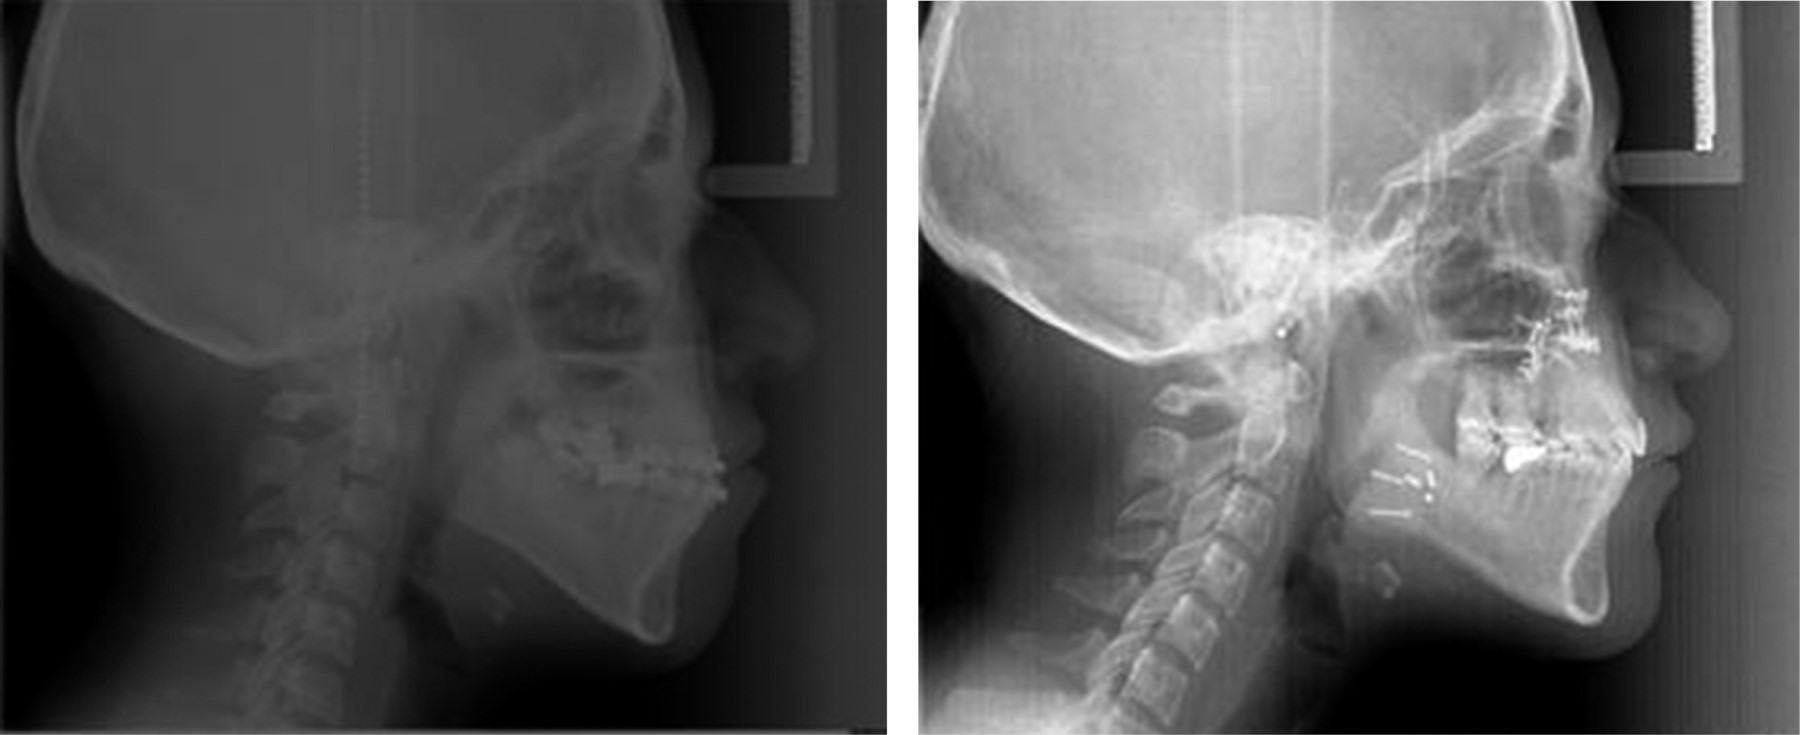

Cephalometric analysis: showed class III skeletal bi-protrusive, vertical excess of the maxilla, vertical growth pattern; dolichofacial, left laterognathia, anterior crossbite, proclination of lower incisors, and retroclination of upper incisors and upper retrochelia (Figure 4).

After 12 months the case was reevaluated with the taking of study and work models, lateral and posteroanterior radiography, and orthopantomography, and together with the Surgery Department of DEPeI, UNAM, the orthognathic surgery was programmed (Figure 8).

Figure 4